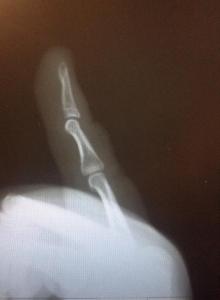

Hola a todos, hay alguien que sepa algo sobre huesos? Compre un varigrip para ejercitar mis dedos. A la semana empece a tener problemas con mi dedo meñique. No podía tocar bien así que fui al medico pero previamente me saque una radiografía. Según el medico tengo un quiste sinovial en la base del dedo y eso es lo que me molesta. Pero la radiografía anda medio rara. Los señores que me tomaron la radiografía me dijeron que mi dedo esta dislocado pero no se nota ninguna deformidad ni duele. Solo a veces al hacer cierto movimiento al tocar guitarra. Le mostré la radiografía al medico y me dijo que es normal, que mis dedos son elásticos y que por eso se dobla hasta donde se dobla. Me esta volviendo loco esto de no poder tocar guitarra y estar con el dedo malo. Alguna opinión?

Ya lo se, solo busco opiniones respecto a la radiografía. Tal vez alguien del foro ya paso por algo similar. Ya fui donde un traumatologo y estoy con desinflamantes, tambien voy a fisioterapia. A mi me parece que la punta del dedo esta dislocada pero segun el traumatologo es normal que mi dedo este asi.